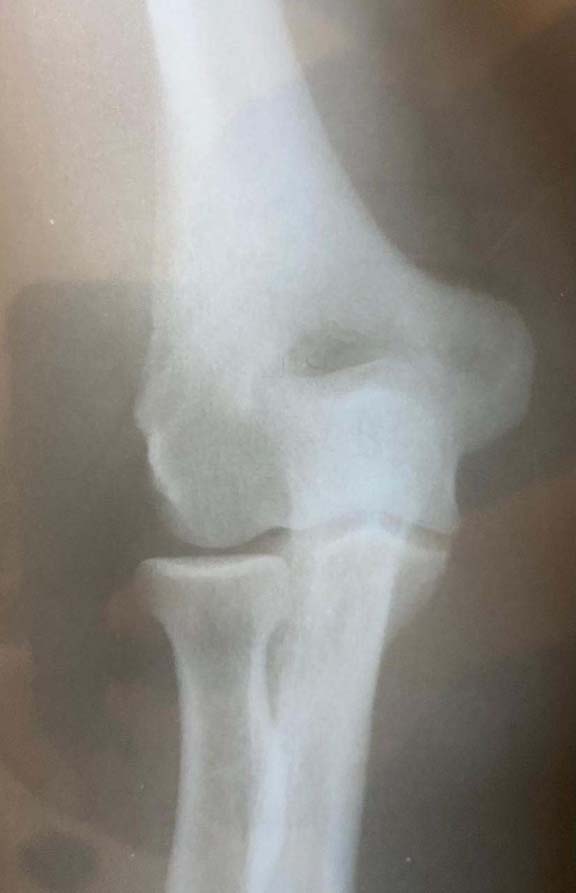

Fraturas do cotovelo

O cotovelo é composto por três ossos: o úmero, ulna e o rádio. As Fraturas do Cotovelo podem acontecer nesses três locais, isoladamente ou em conjunto, acompanhadas ou não por alguma lesão ligamentar ou de nervo. Assim como todas as fraturas, as de cotovelo se dão quando há um rompimento em um ou mais locais do osso. As que ocorrem nessa articulação são: a fratura da cabeça do rádio, a mais comum entre todas; fratura da porção distal do úmero e do olécrano (parte de trás do cotovelo, parte da ulna). As fraturas podem ocorrer em decorrência de uma queda com o braço estendido ou por traumas de alto impacto, como os acidentes automobilísticos. Dor, edema, hematoma e deformidade são os principais sintomas da doença. O diagnóstico e feito através da realização de radiografia e pela tomografia computadorizada. O tratamento pode ser realizado com imobilização gessada para aquelas fraturas bem alinhadas e o tratamento cirúrgico para as fraturas desalinhadas.